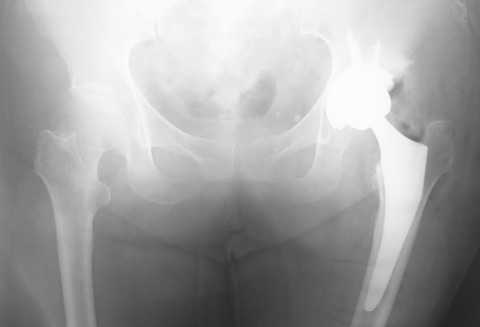

術後の単純X線像ですが、やはり少し大腿骨頚部が短めですね。再置換術のことを考えると、できるだけ大腿骨頚部を温存した方が良いのでは? という意見もあるかもしれません。

しかし、昨今のセメントレスTHAの長期成績を鑑みると、今回の方(70歳台)に再置換術を施行せざるを得なくなる可能性はかなり低いと思います。これぐらいはアリだと思いませんか?